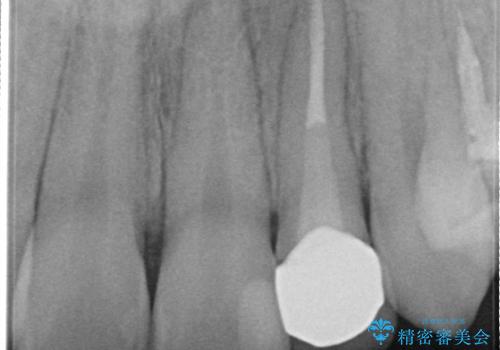

- 以前に被せ物の治療した箇所に汚れが溜まりやすいことを主訴に来院されました。

矯正治療を行なったのち、オールセラミッククラウンにて修復しております。